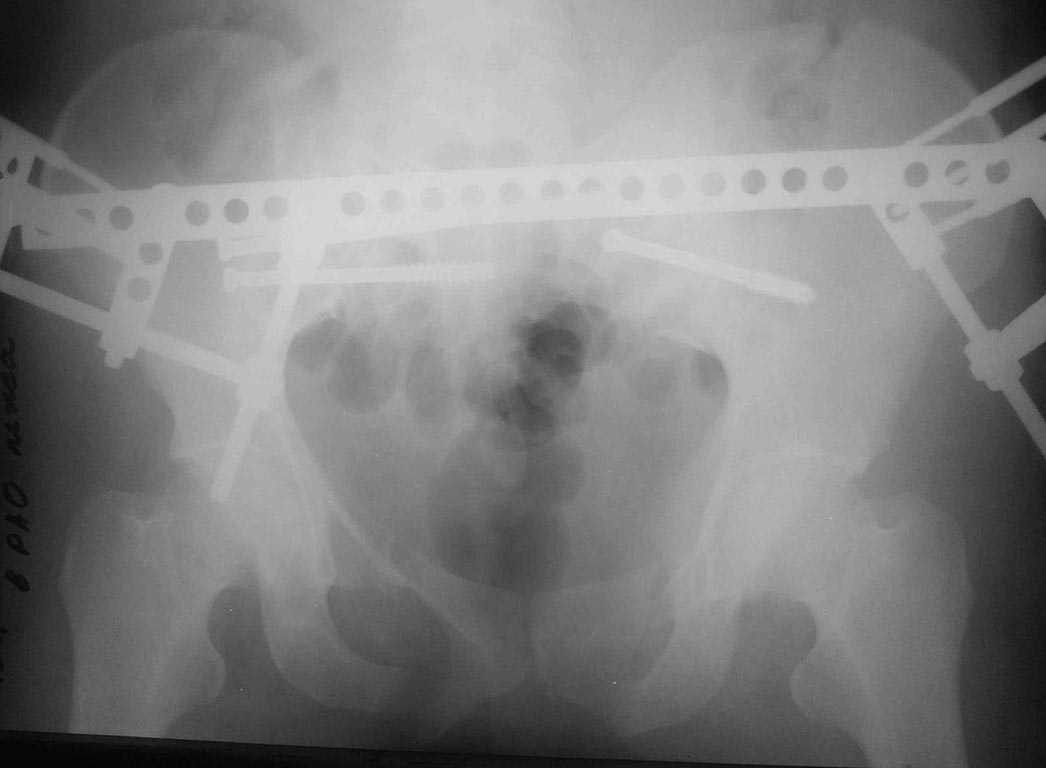

ближайший результат, все сделали закрыто, постараюсь сделать полноценные снммки - это палатником.

По прямой проекции , все очень красиво, поздавляю. для правильности и адекватной оценки положения отломков и металлоконструкции, другие проекции не помешали. Если не секрет ,можно подробнее описать последовательность этапов операции( вы планировали выполнить в несколько этапов), больше интересно приемы репозиции перелома подвздошной кости слева,т.к делали закрыто.

Сначала стабилизировали правую половину (крестец), вторым этапом сначала плечо, потом задние отделы слева, дальше аппарат спереди. Репозиция в положении на животе, свесил таз со стола, согнул ногу и тракция в этом положении.

аппарат недель на 6, но без нормального стола и ЭОПа делать проблематично, особенно крыло, толком проекции вывести не мог, прошел выше чем хотелось. Илиосакральные выинты тоже идут как-то подозрительно, хотя под ЭОПом выглядело все ОК, да и по ощущениям тоже (никаких провалов), надеюсь, что проекционно - неврологии не появилось.